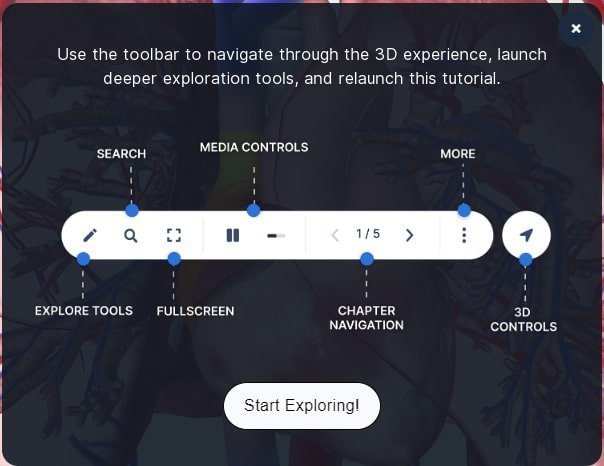

સાઇટ પર નેવિગેશન કેવી રીતે કરશો?

મોબાઇલ કે પીસીમાં human.biodigital.com સાઇટ પર, કોઈ પણ સિસ્ટમ ઓપન કર્યા પછી, માઉસથી ક્લિક-ડ્રગ કરીને કે આંગળીથી એનેટોમીનો વ્યૂઇંગ એંગલ બદલી શકાશે.

મોબાઇલ કે પીસીમાં human.biodigital.com સાઇટ પર, કોઈ પણ સિસ્ટમ ઓપન કર્યા પછી, માઉસથી ક્લિક-ડ્રગ કરીને કે આંગળીથી એનેટોમીનો વ્યૂઇંગ એંગલ બદલી શકાશે.

પીસીમાં માઉસ સ્ક્રોલ અપ કે ડાઉન કરીને ઝૂમ-ઇન કે આઉટ કરી શકાશે. મોબાઇલમાં આ જ કામ આંગળીથી કરી શકાશે.

પીસીમાં માઉસ સ્ક્રોલ અપ કે ડાઉન કરીને ઝૂમ-ઇન કે આઉટ કરી શકાશે. મોબાઇલમાં આ જ કામ આંગળીથી કરી શકાશે.

આખેઆખી એનેટોમીની જગ્યા બદલવી હોય, તો પીસીમાં શિફ્ટ કી પ્રેસ કરી, માઉસથી ડ્રેગ કરો. મોબાઇલમાં એક સાથે બે આંગળીથી ડ્રેગ કરીને એનેટોમીની પોઝિશન બદલી શકાશે.

આખેઆખી એનેટોમીની જગ્યા બદલવી હોય, તો પીસીમાં શિફ્ટ કી પ્રેસ કરી, માઉસથી ડ્રેગ કરો. મોબાઇલમાં એક સાથે બે આંગળીથી ડ્રેગ કરીને એનેટોમીની પોઝિશન બદલી શકાશે.

જુદા જુદા ભાગ ક્લિક કરીને માત્ર એ જ દેખાય એવું પણ કરી શકાશે. જેમ કે હૃદયના વિવિધ ભાગ પર ક્લિક કરી, તેના વિશે વધુ જાણી શકાશે. પીસીમાં દરેક ભાગ વિશે ઘણી વિસ્તૃત માહિતી મળશે.

જુદા જુદા ભાગ ક્લિક કરીને માત્ર એ જ દેખાય એવું પણ કરી શકાશે. જેમ કે હૃદયના વિવિધ ભાગ પર ક્લિક કરી, તેના વિશે વધુ જાણી શકાશે. પીસીમાં દરેક ભાગ વિશે ઘણી વિસ્તૃત માહિતી મળશે.

દરેક રચના જોતી વખતે એક ટૂલબાર ઓપન કરી શકાય છે. તેની મદદથી તમે ૩ડી વ્યૂઇંગ એક્સ્પિરીયન્સમાં વધુ કંટ્રોલ મેળવી શકશો.

દરેક રચના જોતી વખતે એક ટૂલબાર ઓપન કરી શકાય છે. તેની મદદથી તમે ૩ડી વ્યૂઇંગ એક્સ્પિરીયન્સમાં વધુ કંટ્રોલ મેળવી શકશો.